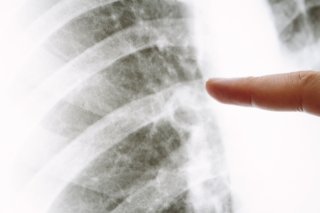

前回は胸部Ⅹ線検査の精度について

書きましが、肺に“がん”があっても

2cm以下のものは殆ど見つかっておらず、

装置の性能や読影者(診断する人)の

力量にも左右されている感じなのです。

また、胸部Ⅹ線検査では肺がんだけでなく

肺炎や結核、気胸をはじめとして肺の様子

を診ているというのは皆さんもご存知と

実際に見えているのは肺の70%以下だった

ことを知っている人はあまり居ないのでは